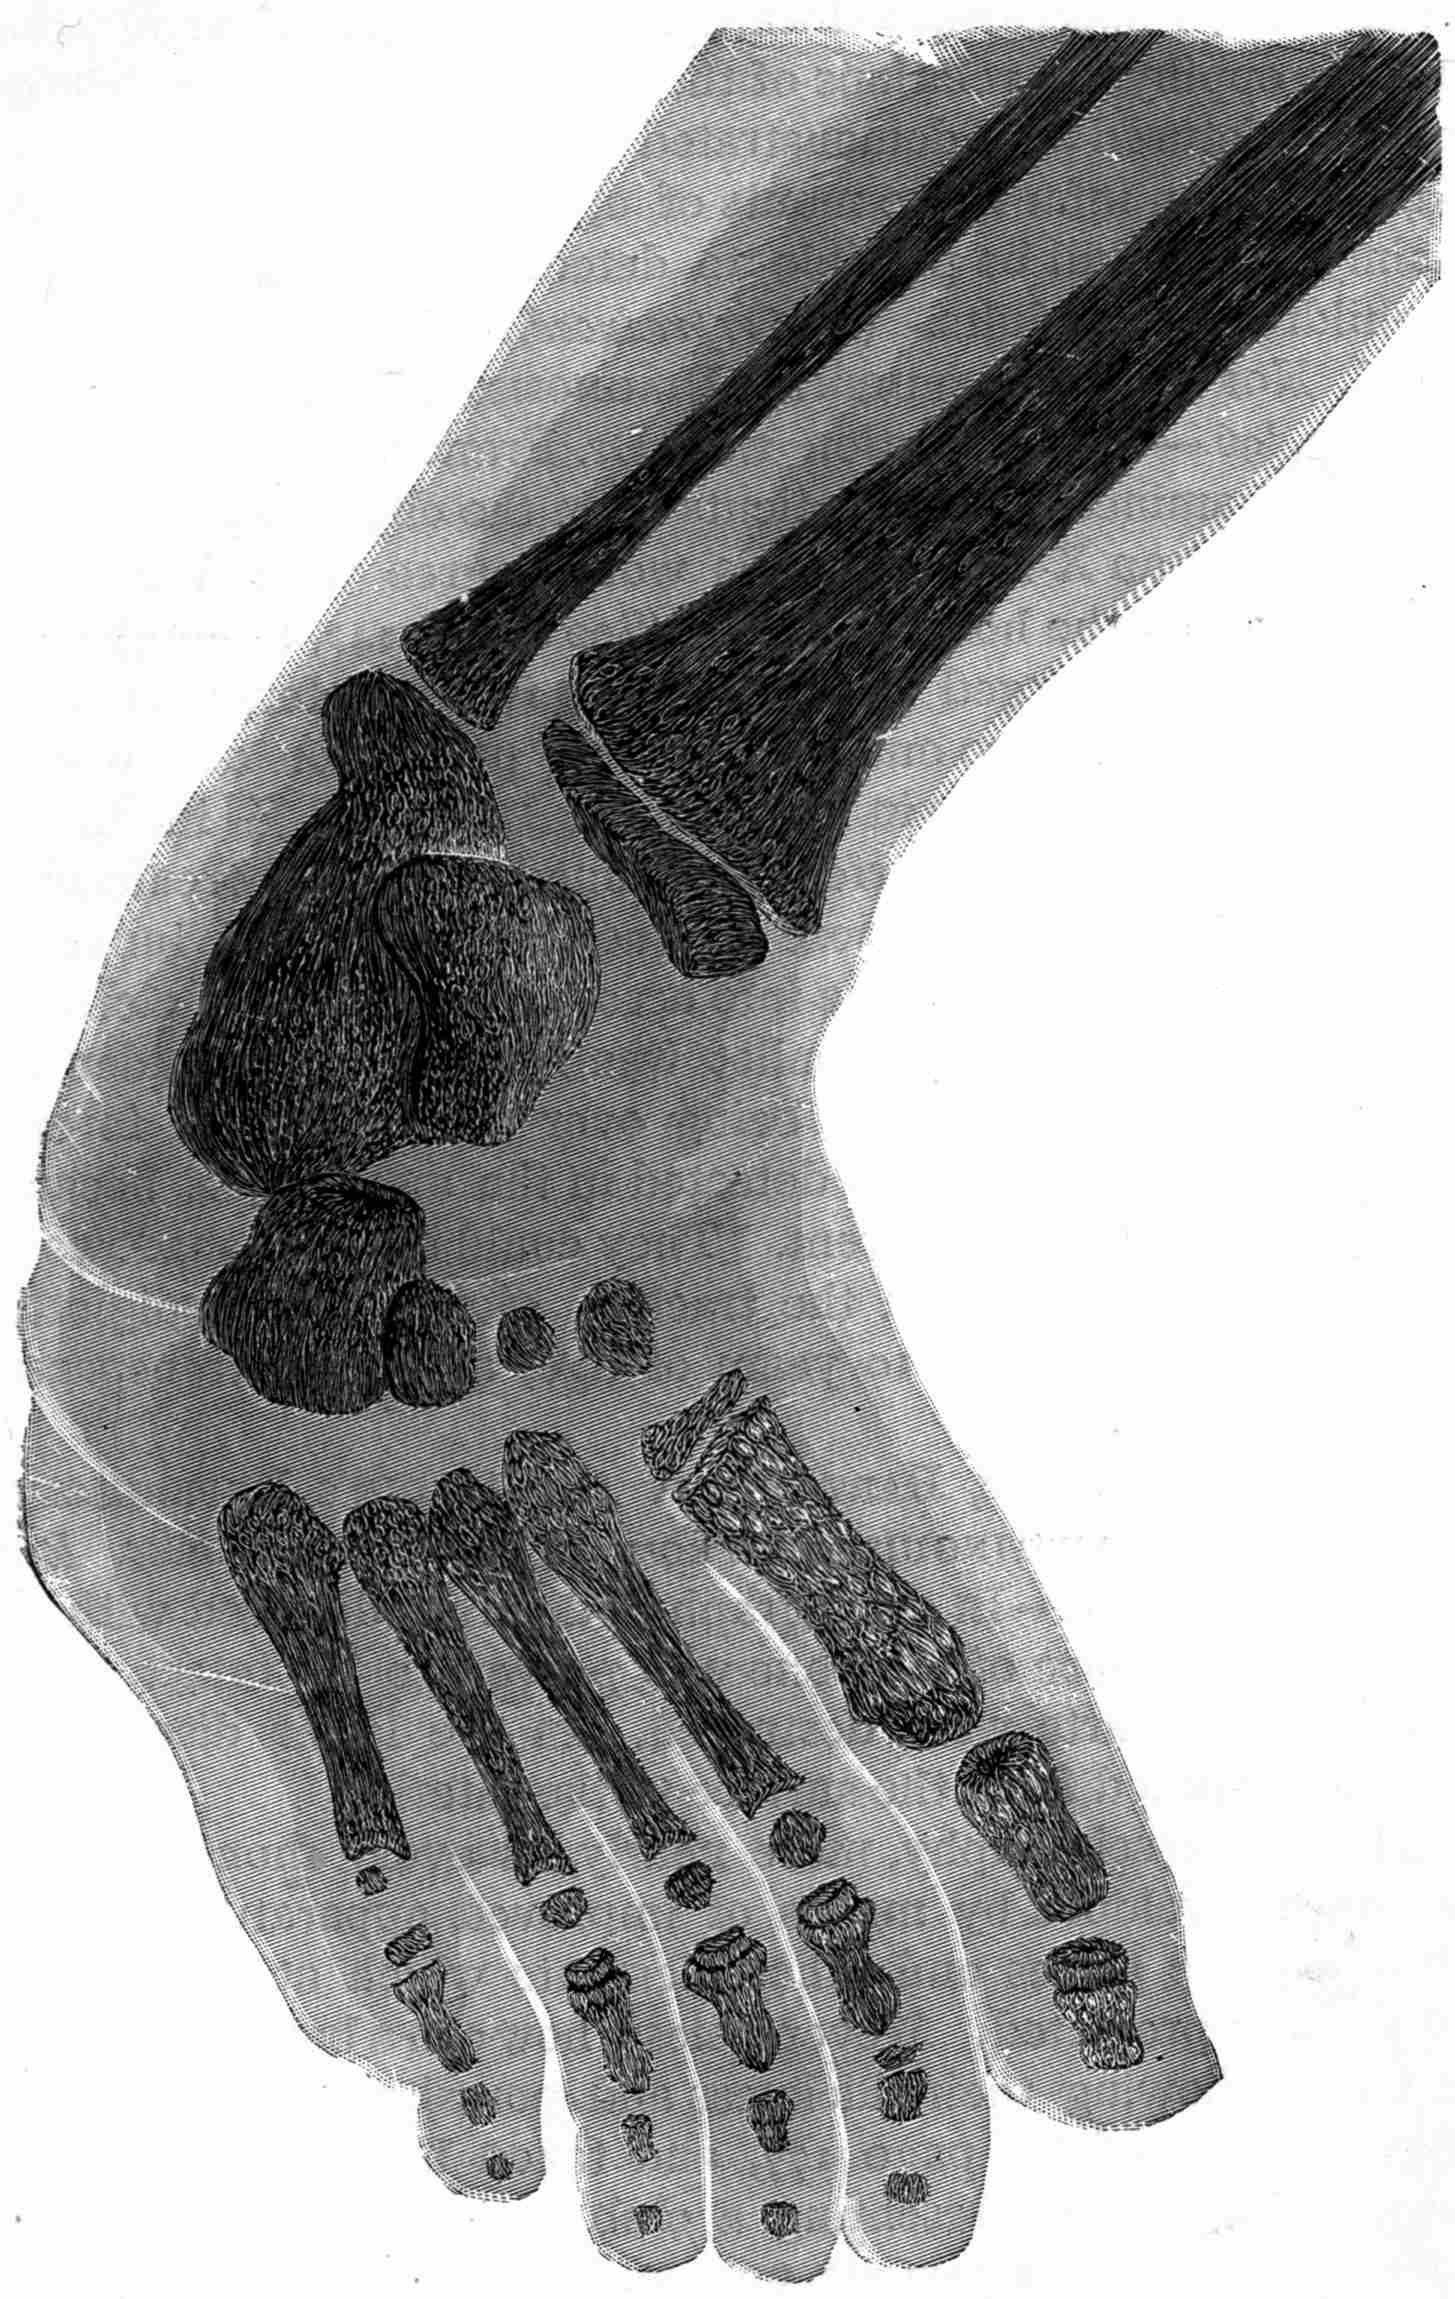

| 159. | Bas-relief Sciagraphs by X-rays. | Carpentier and Miller |

| 161. | Mineral Substances Detected in Vegetable and Animal Products. | Ranwez |